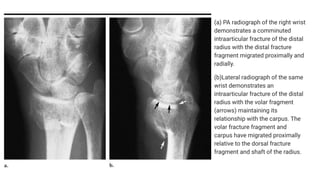

(a) PA radiograph of the right wrist

demonstrates a comminuted

intraarticular fracture of the distal

radius with the distal fracture

fragment migrated proximally and

radially.

(b)Lateral radiograph of the same

wrist demonstrates an

radius with the volar fragment

(arrows) maintaining its

relationship with the carpus. The

volar fracture fragment and

carpus have migrated proximally

relative to the dorsal fracture

fragment and shaft of the radius.